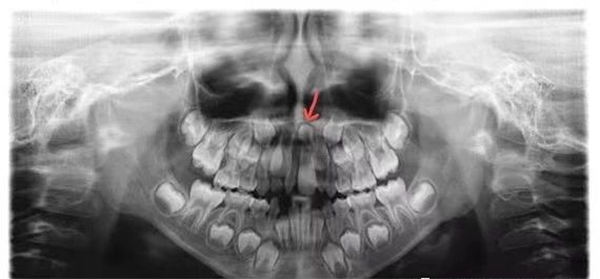

1、全口曲面断层片,亦称口腔全景片(见图1),为二维影像,其优点为可从影像上看到全口每一颗牙齿,其影像信息常作为患儿确诊多生牙的诊断依据。缺点为影像为二维,无法判断多生牙与周围解剖结构三维方向上的关系。

图1 曲面断层片(红色箭头所示为多生牙)